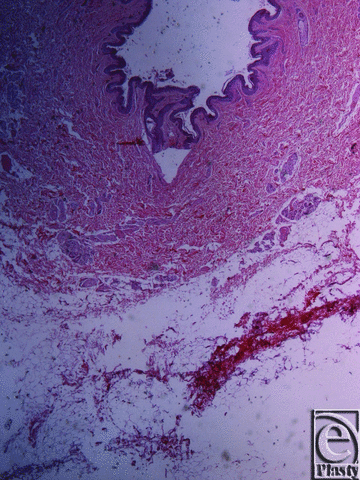

![]() |

| Figure 4. Inframammary crease. Masson trichrome stain ×25. The collagen fibers originate from the muscle fascia and continue their course in the fibrocollagen bundles in a beehive pattern. |

Microscopic evaluation of skin specimens revealed normal dermis and appendages in all cases. In all sections of the inframammary crease specimens, no breast parenchyma was present. In the subcutaneous tissue, there was a well-defined network of dense collagen fibers that create a beehive pattern of the subcutaneous fat (Fig 3). This pattern is denser in the deeper sites in relation to the fascia of the underlying muscle (Figs 4, 5a, and 5b). The collagen fibers network has a broad base of attachment to the dermis. In the sections from the medial sites of the crease, the beehive pattern has the same structure as that described earlier but appears looser. However, it becomes denser in the deeper sites. In the sections of the lateral sites of the crease, the beehive pattern is equally well organized, with broad base attachments of the collagen bundles to the dermis (Fig 6). In some of the cases, the bundles are thinner than those at the other sites. The elastic fibers participate in the formation of the collagen pattern and radiate in a relatively parallel pattern in the reticular dermis and in a perpendicular fashion in the papillary dermis (Fig 7).

The histological results of the specimens of the inframammary crease presented in this study are similar to the results of the previously described studies by Boutros et al3 and Lockwood.4 In the subcutaneous tissue, there is a well-defined network of dense collagen fibers that creates a beehive pattern network of the subcutaneous fat. This network is denser in deeper sites related to the pectoralis muscle fascia. The collagen fibers network has a broad base of attachments to the dermis. In the medial sites of the crease, the beehive pattern has the same structure as described earlier, only looser, which also becomes denser in the deeper sites. In the lateral sites of the crease, the beehive pattern network is just as well organized, with broad base attachments of the collagen bundles to the dermis. In some of the cases, the bundles are thinner than those at the other sites. The elastic fibers participate in the collagen pattern and radiate in a relatively parallel pattern in the reticular dermis and in a perpendicular fashion in the papillary dermis.